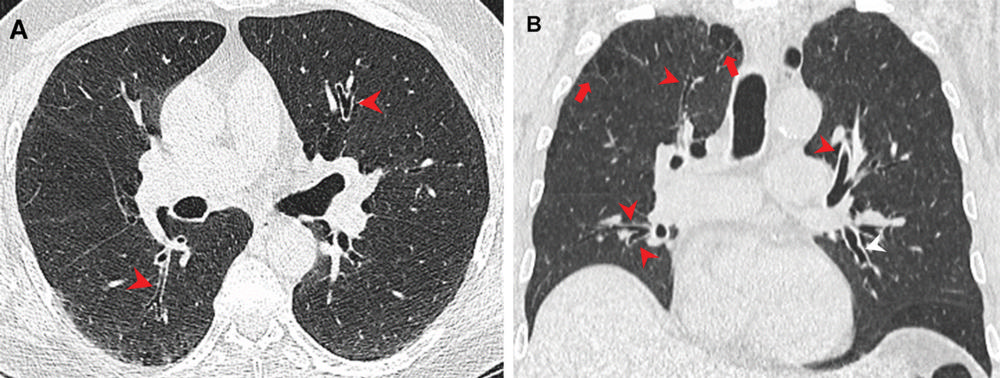

Figure 2. Airway changes in a 66-year-old male marijuana and tobacco smoker. Contrast-enhanced (A) axial and (B) coronal CT images show cylindrical bronchiectasis and bronchial wall thickening (arrowheads) in multiple lung lobes bilaterally in a background of paraseptal (arrows) and centrilobular emphysema. (Murtha, et al.)